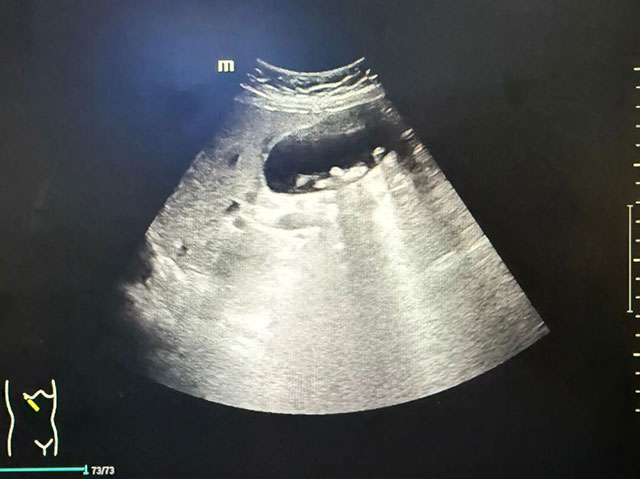

入院后,为了给王婆婆制定最精准的治疗方案,西南医科大学附属医院副院长、胆胰中心主任付文广牵头组织多学科 MDT 会诊,叶明新副主任医师、刘翼副主任医师、石蕾副主任医师、范家皓主治医师等共同讨论。结合后续完善的超声内镜检查结果(提示胆总管多发结石、胆囊多发结石伴胆囊炎),最终确定为她实施“静吸复合全麻下内镜下胆管碎石取石术 + 腹腔镜下胆囊切除术” 的杂交手术方案,一站式解决胆胰问题。

手术当天,在静吸复合全麻下,ERCP(内镜下胆管碎石取石术)率先开始。术中可见胆总管明显扩张(最宽处约 1.2cm),内有多枚约 0.5×0.5cm 的结石样充盈缺损。医师熟练运用取石网篮、取石球囊取出结石,清理胆道后,沿导丝置入胆道塑料支架,确保胆汁引流通畅。